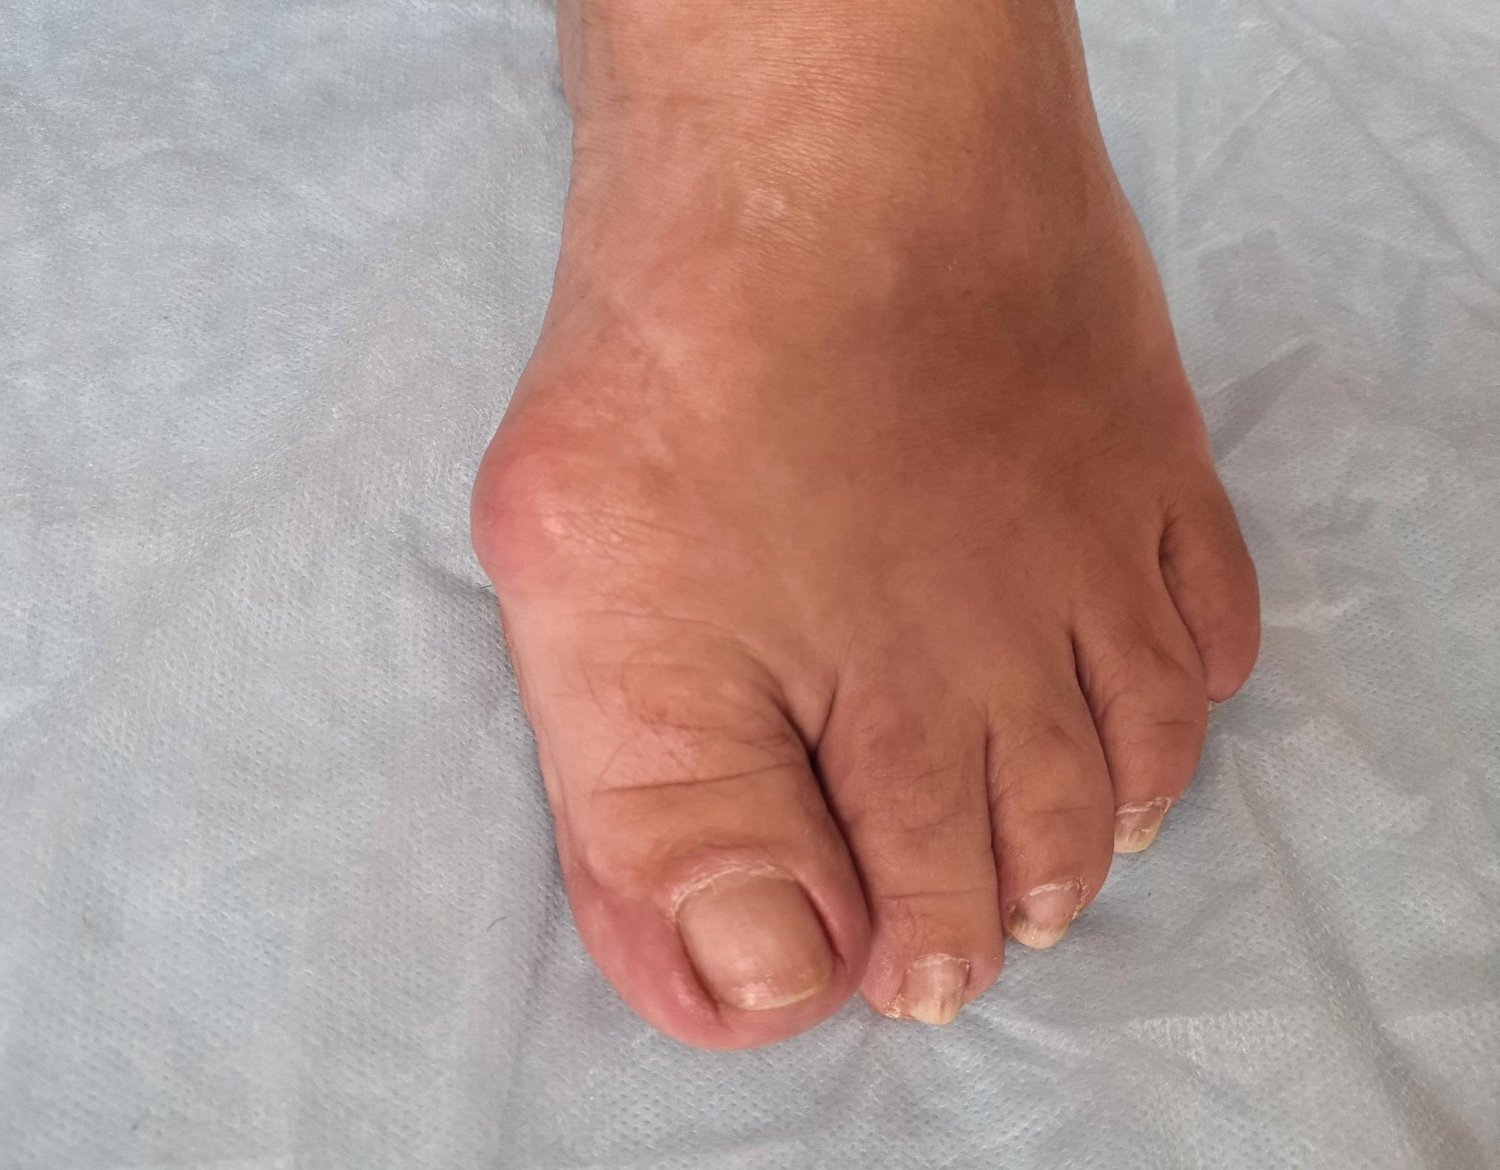

A bunion is a progressive structural deformity of the first joint at the base of the big toe. Often characterized by a visible bony protrusion on the inner side of the foot, a bunion occurs when the big toe (hallux) begins to lean inward toward the second toe. This shift forces the metatarsal bone to protrude outward, creating a misalignment that can make walking painful and finding comfortable footwear a significant challenge.

• Joint Inflammation: The area around the big toe joint frequently appears red, hot, and swollen.

• Callus Development: Thickened skin often forms where the big toe and second toe rub together, or on the side of the bump itself.